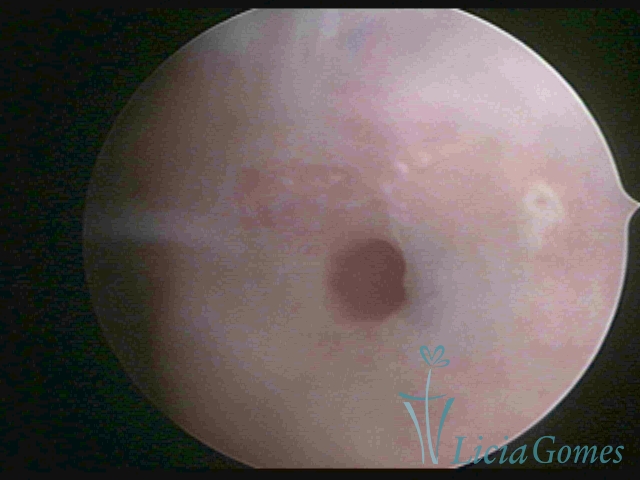

Segunda porção ou setor médio

No terço ou setor médio do canal cervical perdemos o detalhe das papilas, sendo possível a visualização de pregas e criptas. Normalmente observamos os sulcos longitudinais, que são os tecidos mais compactos, com a superfície mais vascularizada, cujos vasos seguem o seu trajeto.